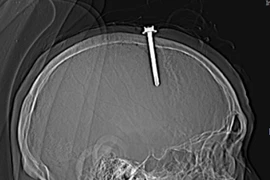

Phẫu thuật thần kinh đòi hỏi độ chính xác cao nhất, đặc biệt khi xử lý các tổn thương sọ não do chấn thương hoặc dị vật nội sọ. Nhờ công nghệ tiên tiến định vị chính xác có thể lấy bỏ toàn bộ dị vật.

Dị vật xuyên màng não là cấp cứu ngoại khoa nghiêm trọng, tùy theo vị trí tổn thương của dị vật mà có thể dẫn đến các biến chứng nguy hiểm như: yếu liệt chi, rối loạn chức năng sống, áp xe não, thậm chí tử vong.